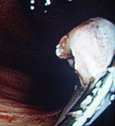

良性の胃ポリープと異なり、大腸ポリープはたとえ現在良性でも将来癌化する可能性があることが知られています。したがってある程度の大きさのポリープは切除することをお勧めします。当院では日帰りで可能ですが

「内視鏡下でポリープ切除が可能」とは言っても、これは手術に該当するものであり、大腸穿孔や術後出血などを引き起こす可能性があります。ポリープを切除した傷が完治するまでの2〜3週間は、食事制限、運動制限、禁酒など合併症予防のために遵守すべき事項があるので、手術を受ける際は厳守して下さい